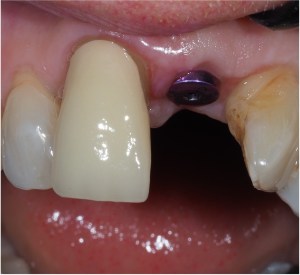

Single implant crowns

Single implant crowns are an excellent way to replace missing teeth. They do not damage the neighbouring teeth and last for a long period of time. These are usually screw retained to allow repair/replacement if there are any maintenance issues.